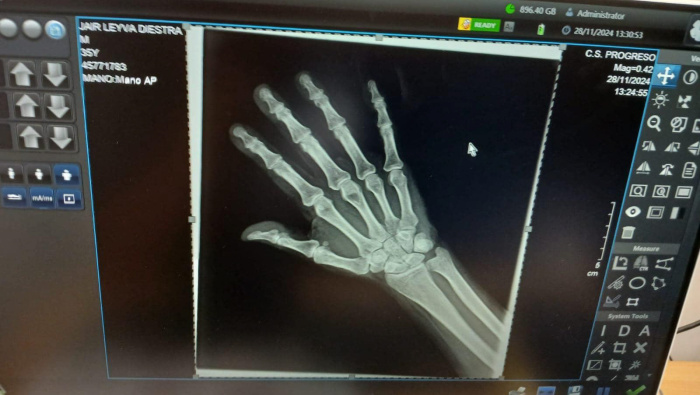

La política del Gobernador Regional Koki Noriega de priorizar mejores condiciones para un servicio de salud óptimo sigue generando resultados concretos. En esta línea, el Centro de Salud Progreso recibió un moderno equipo de rayos X portátil gracias a las gestiones de la Red de Salud Pacífico Norte (RSPN).

El director ejecutivo de la RSPN, Dr. Alex Corcuera Cruz, destacó que esta entrega incluye tecnología de última generación como un detector digital flat panel, una impresora de películas láser, un biombo emplomado, equipo de cómputo y todos los implementos necesarios para el diagnóstico eficiente de enfermedades, en especial la tuberculosis.